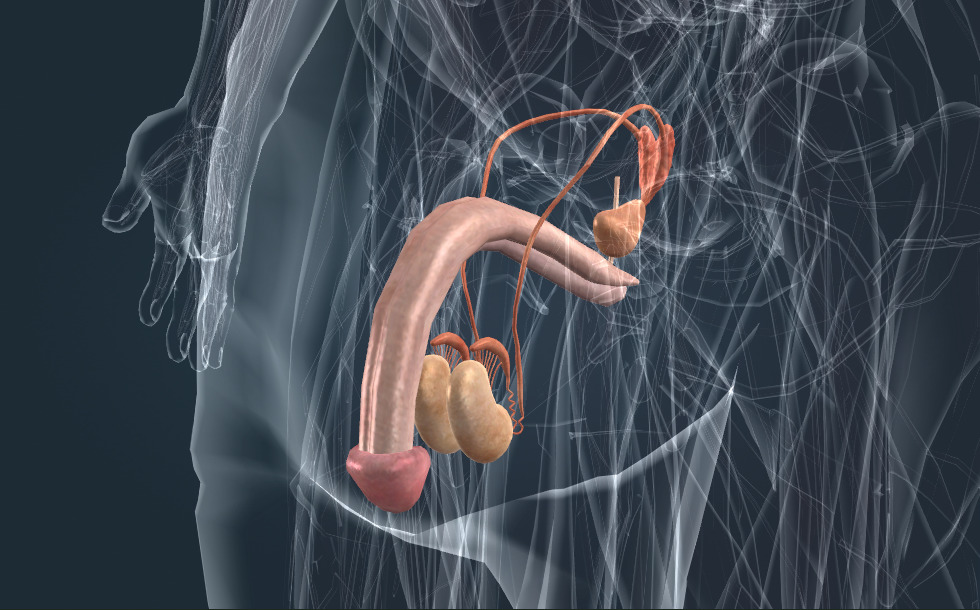

Hệ sinh dục

- tinh hoàn - Nó sản xuất tinh trùng và testosterone (hormone sinh dục nam), có vai trò thúc đẩy sự trưởng thành của tinh trùng, thúc đẩy sự phát triển của lông và các đặc điểm của nam giới.

- mào tinh hoàn - Nó lưu trữ tinh trùng mà tinh hoàn sản xuất ra.

- ống dẫn tinh

- túi tinh - Nó đóng vai trò quan trọng trong sự hình thành của tinh dịch.

- tuyến tiền liệt - Nó đóng vai trò quan trọng trong sự hình thành của tinh dịch. Còn được gọi là tuyến tiền liệt.

Cơ quan sinh dục chịu trách nhiệm cho việc sinh sản, chúng tạo ra giao tử. Trong quá trình thụ tinh, trứng hợp nhất với một tinh trùng tạo thành hợp tử, từ đó phôi phát triển. Các tuyến sinh dục ở nam giới là tinh hoàn, có vai trò sản xuất ra tinh trùng. Tinh trùng được lưu trữ trong mào tinh hoàn; trong quá trình xuất tinh, tinh trùng được phóng ra ngoài cùng với tinh dịch qua niệu đạo. Tinh dịch được sản xuất bởi tuyến tiền liệt và túi tinh.

Cơ quan sinh dục chịu trách nhiệm cho việc sinh sản, chúng tạo ra giao tử. Trong quá trình thụ tinh, trứng hợp nhất với một tinh trùng tạo thành hợp tử, từ đó phôi phát triển. Các tuyến sinh dục ở nam giới là tinh hoàn, có vai trò sản xuất ra tinh trùng. Tinh trùng được lưu trữ trong mào tinh hoàn; trong quá trình xuất tinh, tinh trùng được phóng ra ngoài cùng với tinh dịch qua niệu đạo. Tinh dịch được sản xuất bởi tuyến tiền liệt và túi tinh.